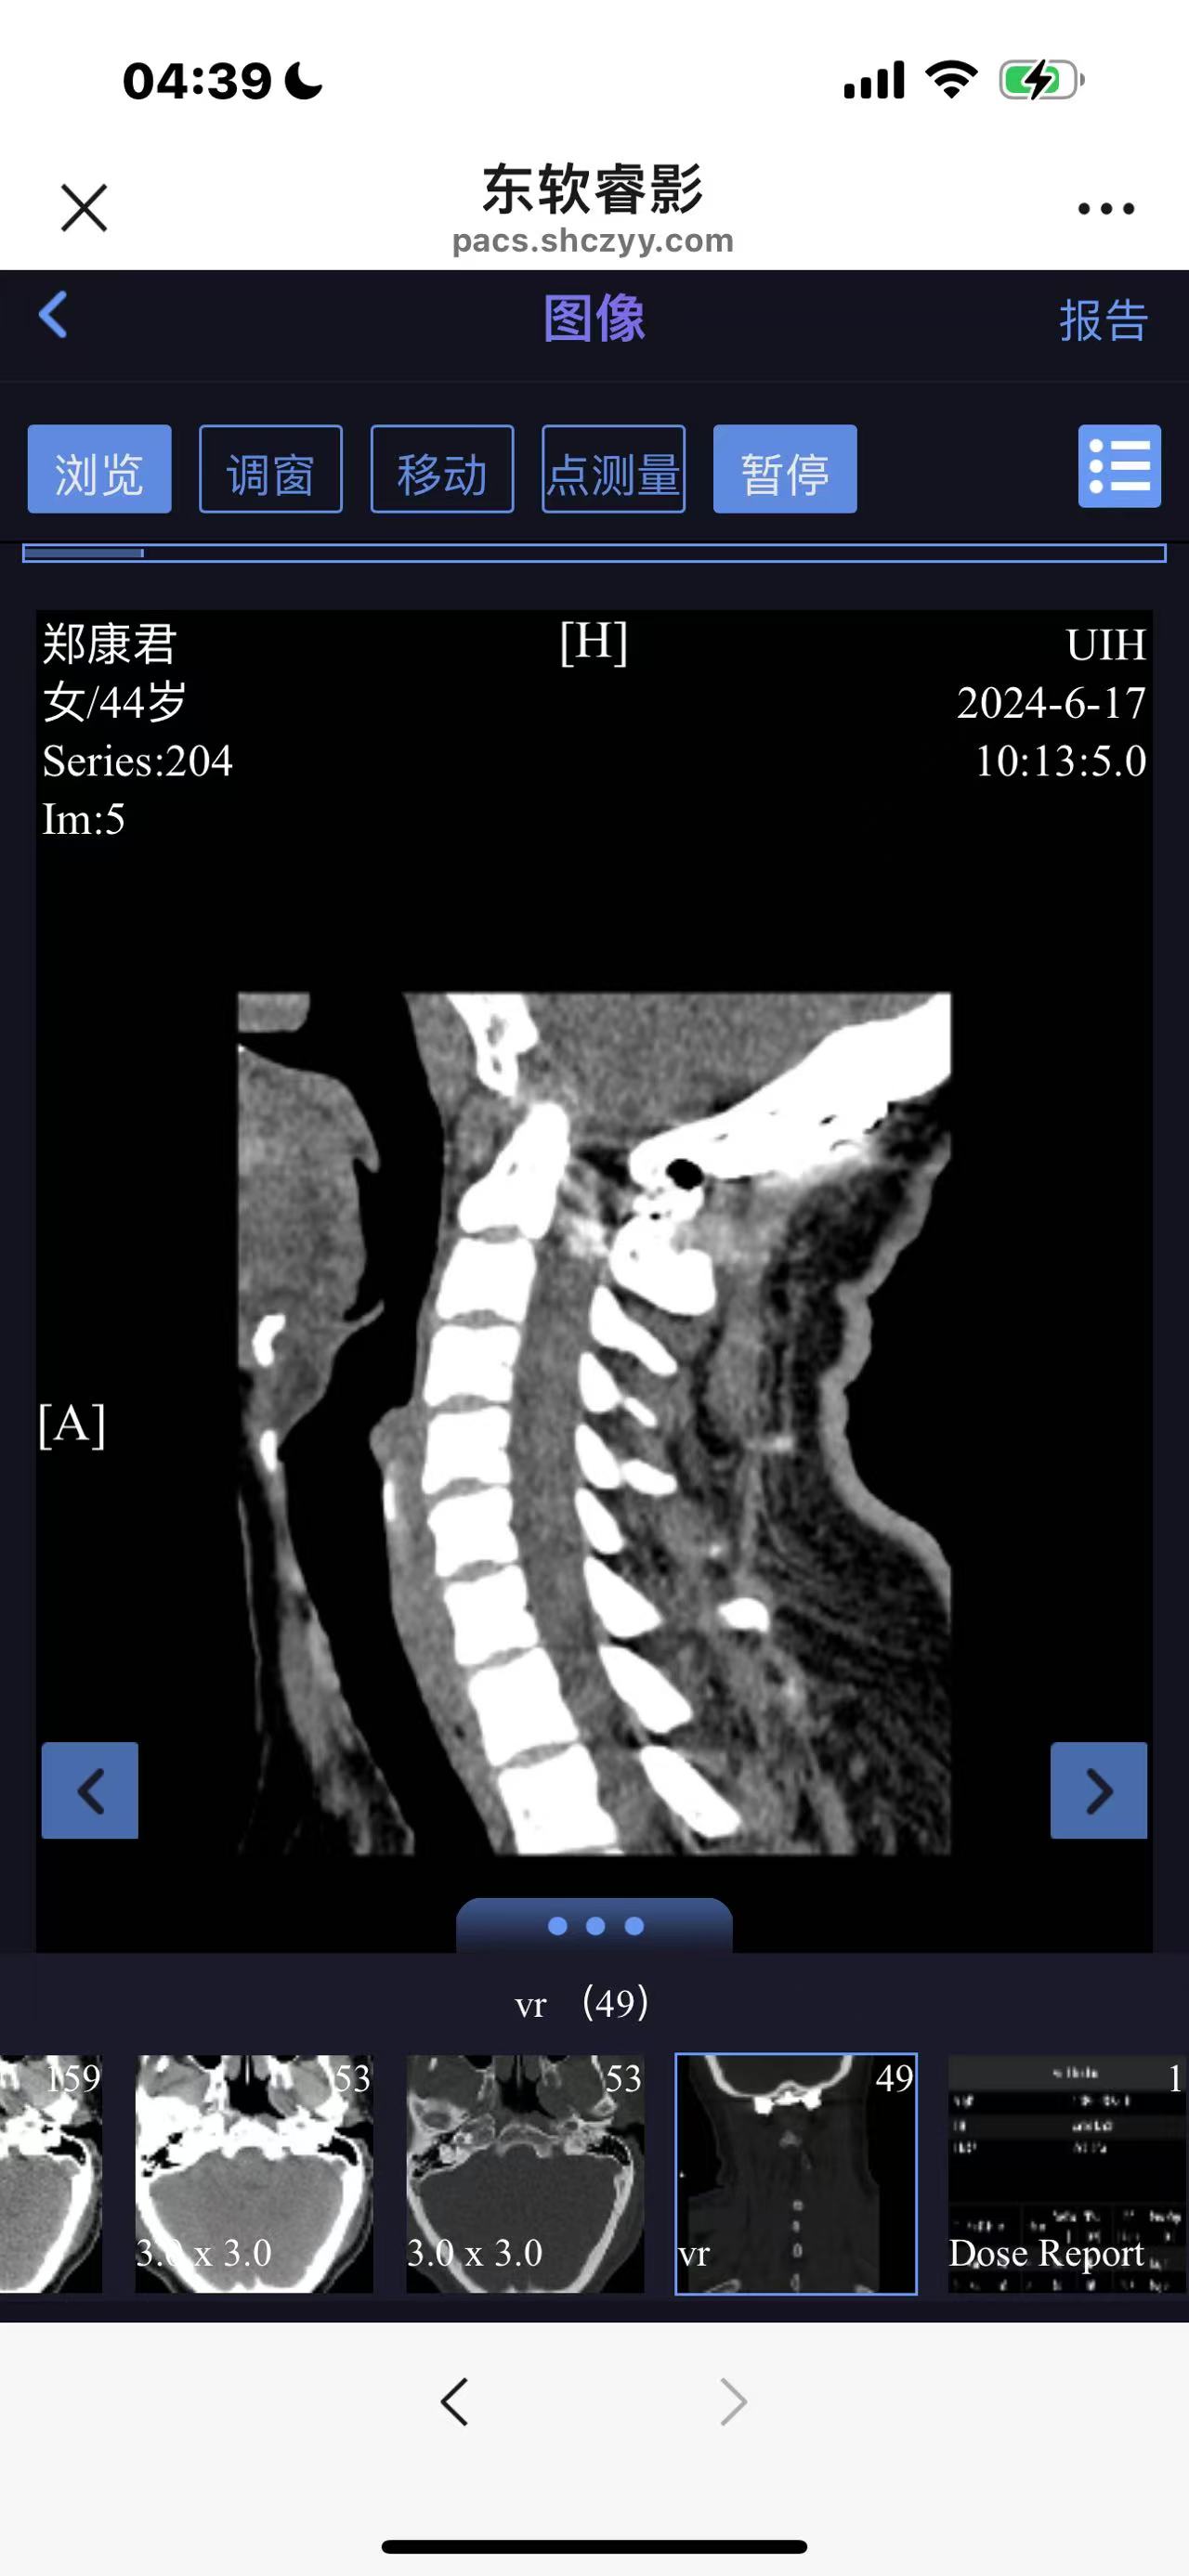

• 诊断:寰枢椎脱位

• 影像:

• 日期:2024.06